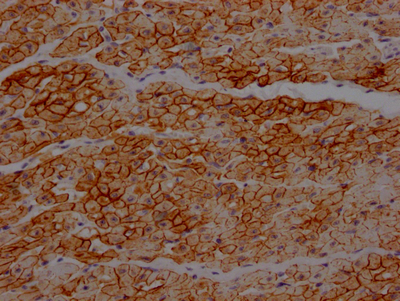

IHC image of CSB-RA271553A0HU diluted at 1:100 and staining in paraffin-embedded human heart tissue performed on a Leica BondTM system. After dewaxing and hydration, antigen retrieval was mediated by high pressure in a citrate buffer (pH 6.0). Section was blocked with 10% normal goat serum 30min at RT. Then primary antibody (1% BSA) was incubated at 4℃ overnight. The primary is detected by a Goat anti-rabbit IgG polymer labeled by HRP and visualized using 0.05% DAB.

IHC image of CSB-RA271553A0HU diluted at 1:100 and staining in paraffin-embedded human skeletal muscle tissue performed on a Leica BondTM system. After dewaxing and hydration, antigen retrieval was mediated by high pressure in a citrate buffer (pH 6.0). Section was blocked with 10% normal goat serum 30min at RT. Then primary antibody (1% BSA) was incubated at 4℃ overnight. The primary is detected by a Goat anti-rabbit IgG polymer labeled by HRP and visualized using 0.05% DAB.